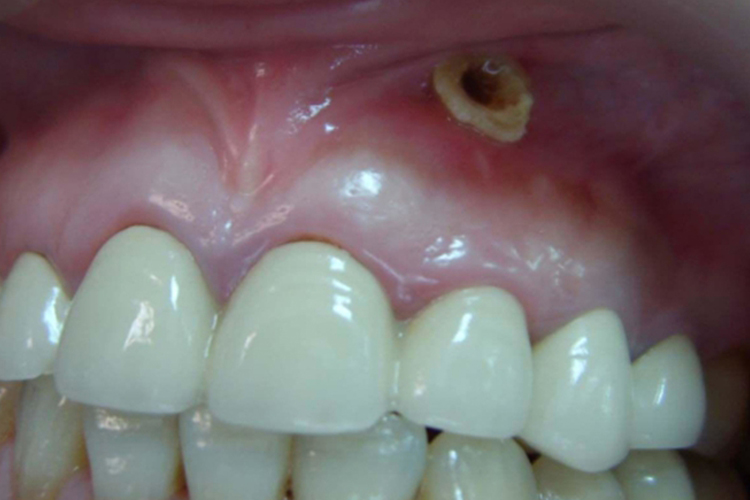

牙龈有洞眼通常指牙龈的窦道开口,常发生在有窦型慢性根尖周炎者,可查及位于患牙根尖部的唇颊侧牙龈表面的窦道口,部分患者可探及牙周袋。叩诊反应无明显异常或仅有不适感,一般牙不松动,部分患者出现扪诊疼痛感。对于存在慢性牙周脓肿的患者,可见有针尖大开口或肉芽组织增生的开口,压时有少许脓液流出。可有咬合不适感或钝痛,当脓液引流不畅时。

慢性根尖周炎:牙髓组织和根尖周组织通过根尖孔密切相连,牙髓组织中的病变产物细菌及其毒素等可通过根尖孔扩散到根尖周组织,引起根尖周病,根尖周病加重后可在牙龈部出现瘘管。

慢性牙周脓肿:可能由多种因素导致,如深牙周袋内壁的化脓性炎症向深部结缔组织扩展、进行治疗时将牙石碎片推入牙周袋深部组织或损伤牙龈组织等,可引起根尖损害,出现瘘管症状。